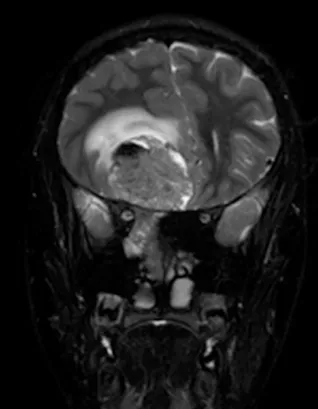

脑部和鼻旁窦计算机断层扫描(CT)和磁共振成像(MRI)扫描显示右侧存在5.5×4.4×5.6厘米肿块,起源于鼻腔、筛窦和蝶窦区域。肿块已侵蚀筛板进入前颅窝。该肿块在CT扫描上未出现钙化(图1),与脑组织等密度,伴有不均匀对比增强。肿块在T1和T2加权MR图像上(图2、3、4)与脑组织等信号,钆增强后显示不均匀强化。注意到周围存在血管源性脑水肿和占位效应。脊柱MRI未见转移证据。

图4:冠状位T2加权MRI扫描,证实颅内肿瘤成分的不均匀实性和囊性性质。病灶周围水肿以及肿瘤相关的中线移位清晰可见。